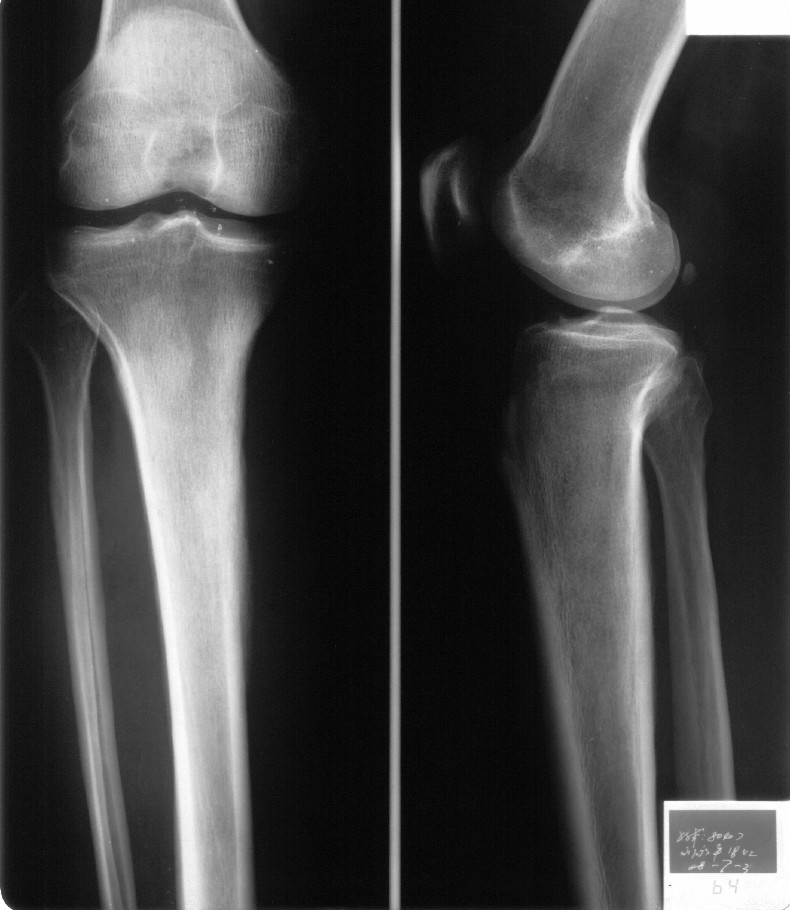

男,42岁。4个月前钢筋钝伤右侧小腿部,当时因无明显外伤,未引起重视。一周后因受伤腿部疼痛,发现肿胀,随后到当地医院进行检查(2008年4月16日)。因未发现骨质异常未引起重视,仅仅进行口服抗生素治疗处理。经过一段时间治疗但未见明显治疗效果在5月29日又进行x线检查,发现有胫骨密度上段密度增高,又进行抗炎治疗,仍未见效果。又在7月3日进行x线检查,仍然报告有胫骨上端密度增高,并建议ct检查。以下是相关检查结果:

髓腔密度呈絮状增高,胫骨上端内侧可见层状骨膜反应,考虑骨髓炎.

髓腔密度呈絮状增高,胫骨上端内侧可见层状骨膜反应,肌间隙模糊,考虑骨髓炎.

该患者到某三级医院进行会诊,并重新作了平片检查,认为畸形性行骨炎: